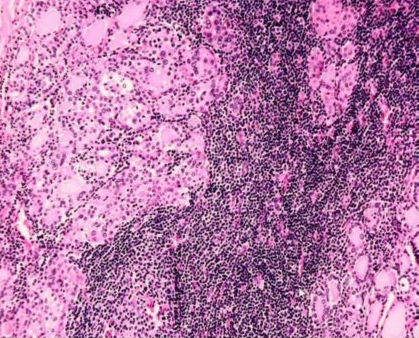

Chronic lymphocytic thyroiditis / Hashimoto’s thyroiditis

Chronic lymphocytic thyroiditis / Hashimoto’s thyroiditis, magnified